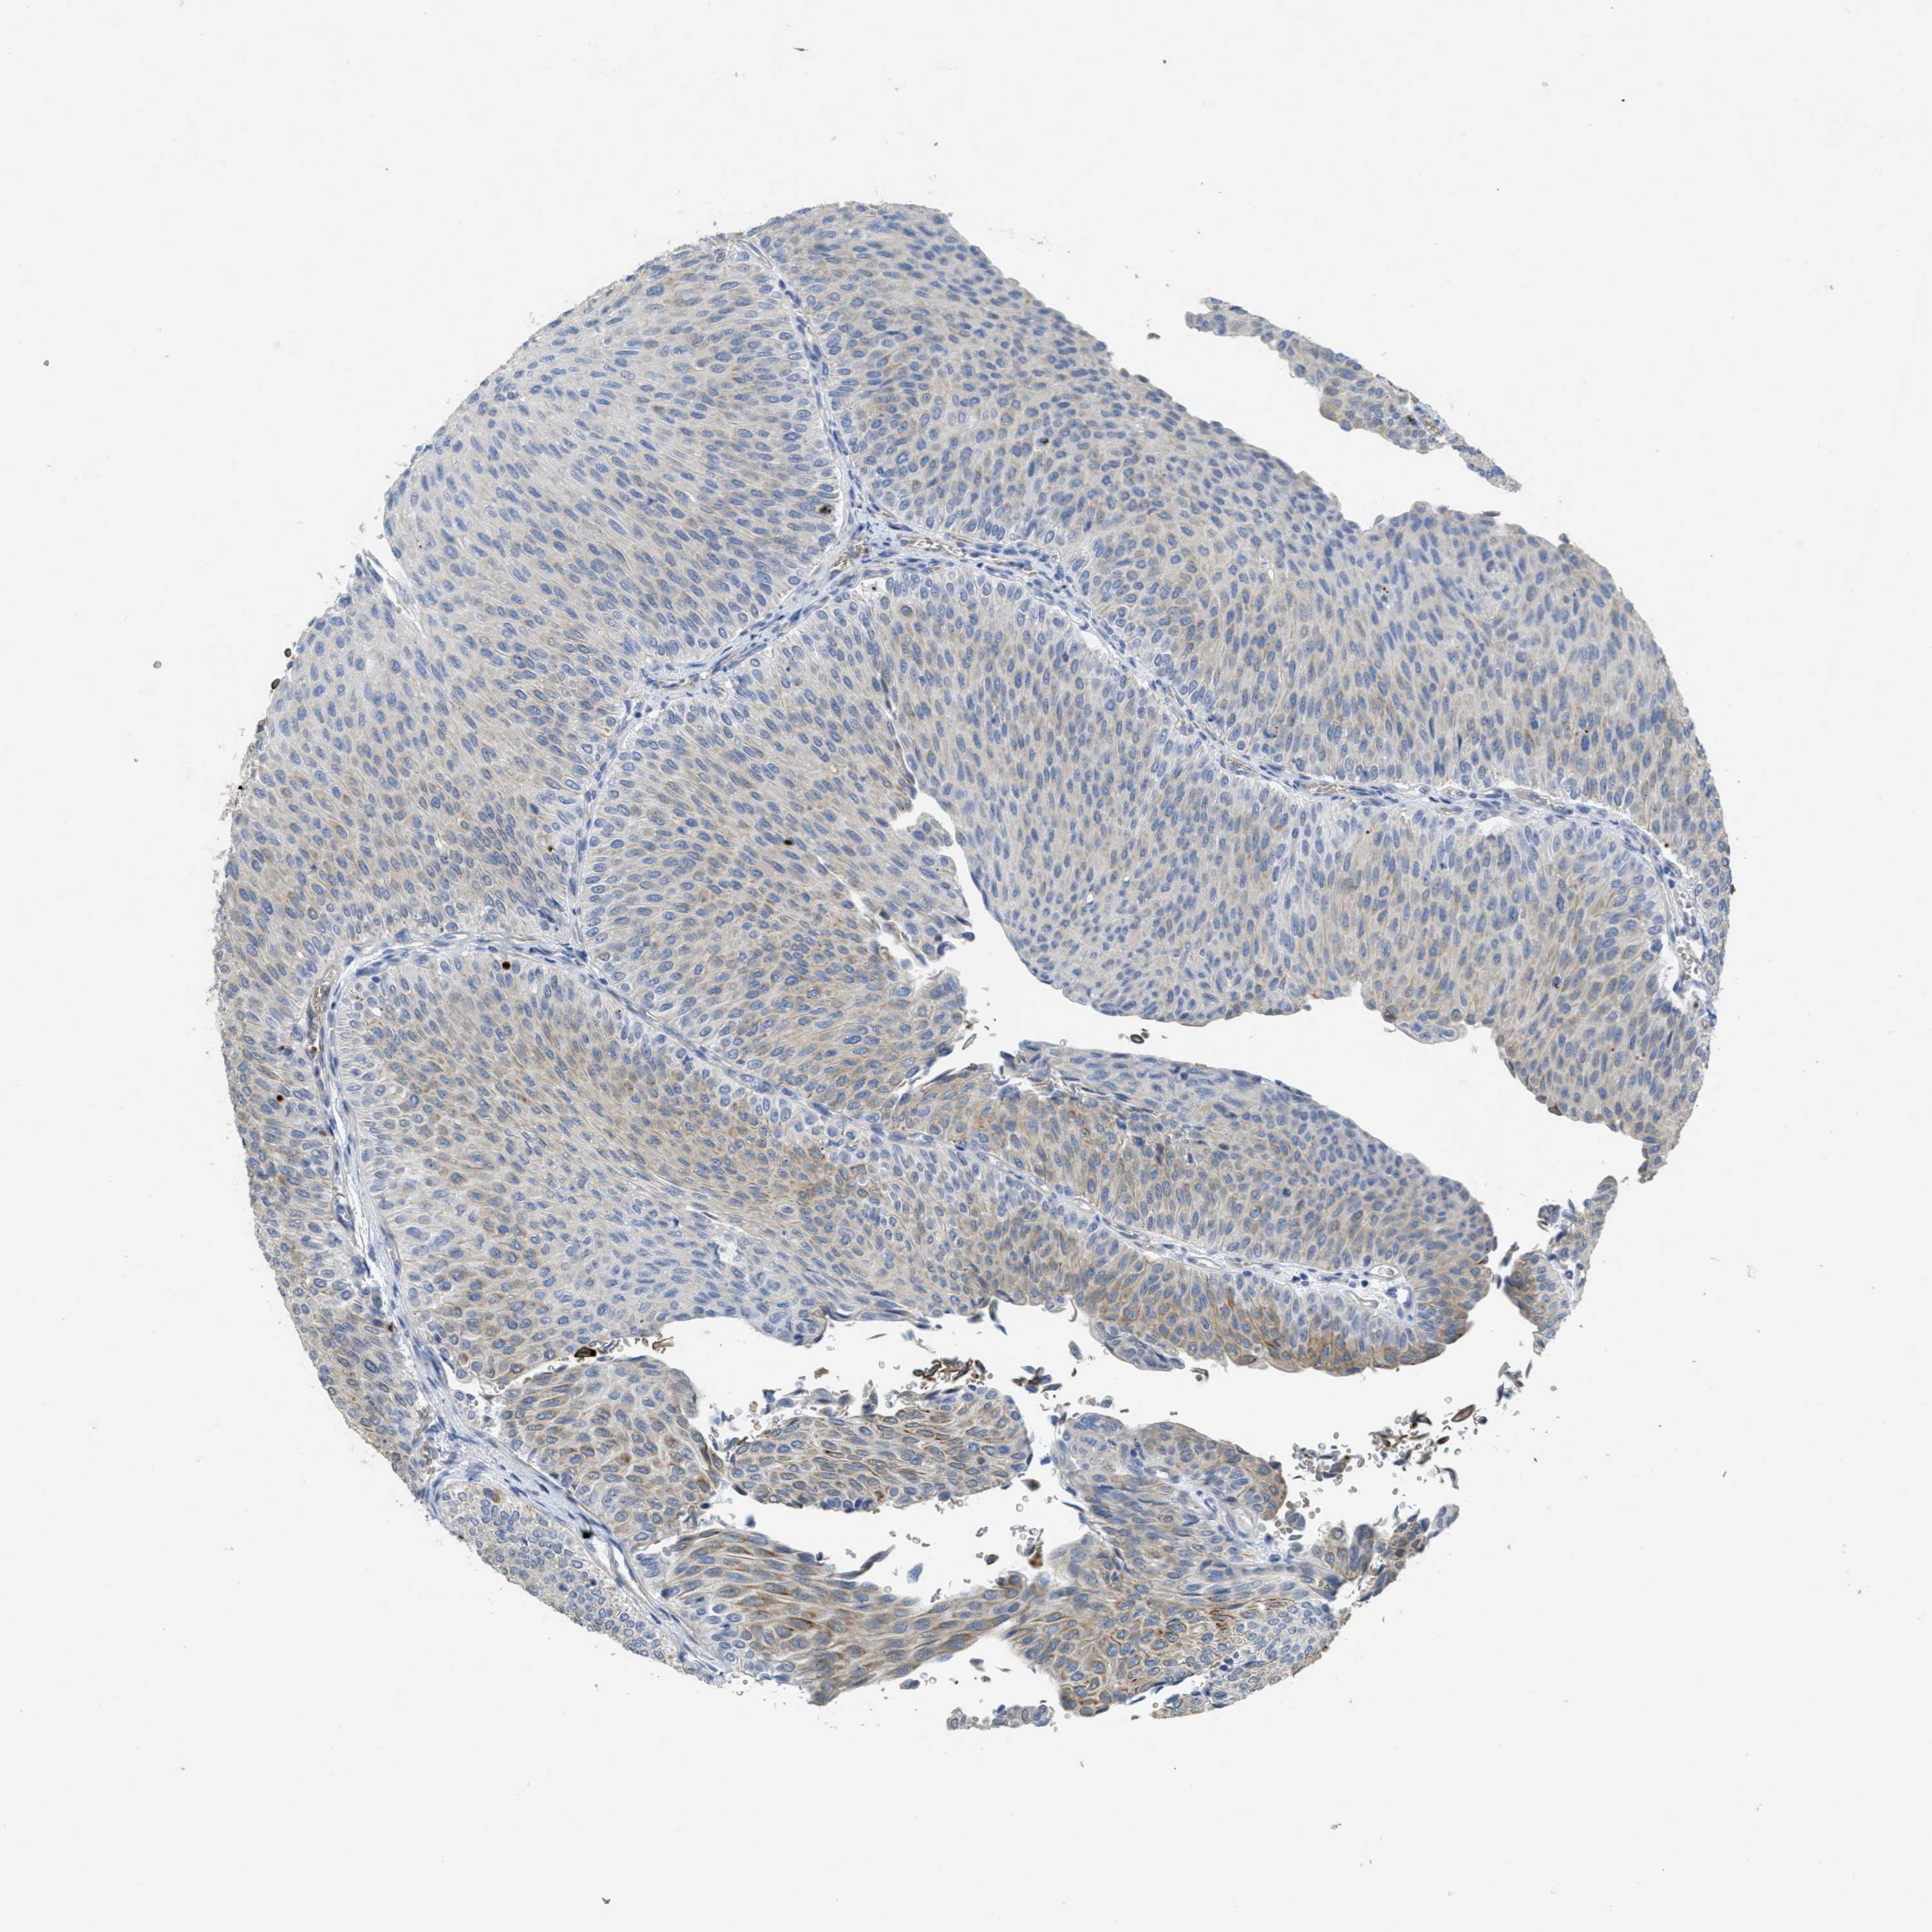

UROTHELIAL CANCER - Protein expressioni

A mouse-over function shows sample information and annotation data. Click on an image to view it in a full screen mode. Samples can be filtered based on level of antibody staining by selecting one or several of the following categories: high, medium, low and not detected. The assay and annotation is described here.

Note that samples used for immunohistochemistry by the Human Protein Atlas do not correspond to samples in the TCGA dataset.

Antibody stainingi

Antibody staining in the annotated cell types in the current human tissue is reported as not detected, low, medium, or high, based on conventional immunohistochemistry profiling in selected tissues. This score is based on the combination of the staining intensity and fraction of stained cells.

Each image is clickable and will lead to virtual microscopy that enables deeper exploration of all samples and also displays staining intensity scores, fraction scores and subcellular localization as well as patient and tissue information for each sample.

Antibody HPA017642

Staining

High

Medium

Low

Not detected

Intensity

Strong

Moderate

Weak

Negative

Quantity

>75%

75%-25%

<25%

None

Location

Nuclear

Cytoplasmic/membranous

Cytoplasmic/membranous,nuclear

Urothelial carcinoma, Low grade

Urothelial carcinoma, High grade